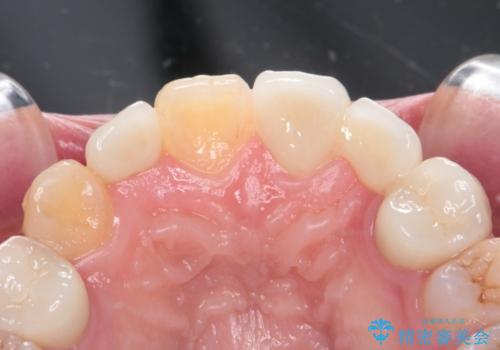

前歯の審美的なブリッジ (歯列矯正後)

- 66万円 内訳:ジルコニアクラウンブリッジ(スペシャル) 15.4万円×4本、仮歯 1.1万円×4本費用は治療当時の料金となります

矯正治療で歯の位置を整えてからブリッジを入れると歯の幅を自由に設定できるため、左右対称にできます。結果矯正なしでいきなりセラミックにする場合と異なり、無理に角度を変えたりする必要がなく、神経をなるべく温存したまま審美的なセラミック治療が行えます。